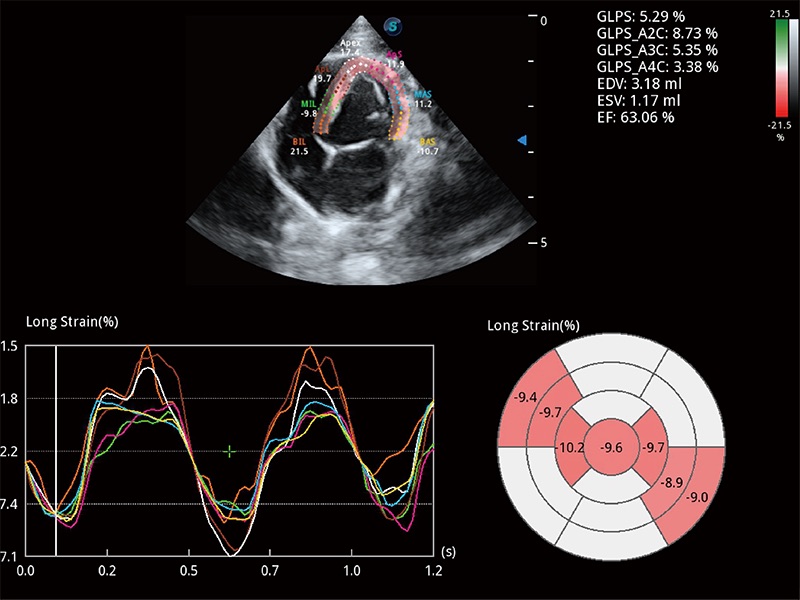

通过心肌识别技术与二维斑点追踪技术相结合,对心脏的超声图像进行量化分析。计算心肌17个节段的应变、应变率、速度、位移等,并通过牛眼图的形式进行呈现。

通过360度任意调节3条M型取样线,在同一心动周期上观察心脏不同位置的运动曲线,得到准确的心功能测量数据,有效评估心肌运动及左心室功能。

能够基于左心室壁追踪和辛普森法,自动计算射血分数,支持多个可移动点描迹,与手动测量相比,极大节省了动物医生的时间和精力。